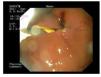

¿ Figure 1. With the linear array echoendoscope located in the stomach, the left bile duct was targeted and an antegrade cholangiography was performed, showing diffuse bile duct dilation that reached the distal common bile duct. A guide wire was inserted through the needle into the bile duct, and manipulated until we managed to get through the distal common bile duct stenosis, papilla and duodenal stent into the duodenal lumen. We extracted both ends of the guide wire with a rendezvous technique, and when the frontal view endoscope was inserted over the transgastric end of the wire, the gastric perforation was clearly shown with obvious pneumoperitoneum (arrow).

A 43 year-old male with unresectable pancreatic head adenocarcinoma diagnosed 3 months before, was admitted because of incoercible vomiting and jaundice (bilirrubin level of 9.4 mg/dL). Gastroscopy showed tumoral infiltration of the duodenal bulb which prevented access to the ampulla. After informed consent process in which we discuss with the patient the available options including EBPD, another endoscopic session was planned in order to treat both digestive and biliary obstructions. Anticipating that EBPD could be necessary, the patient was placed in supine position under sedation with propofol. We started the procedure by deploying of a 14 cm long self-expandable enteral metallic stent (SEMS) (Hanarostent, Sewoon Medical, Korea) through the duodenal stenosis. After placing the duodenal stent we tried to access the second duodenal loop through the stent, but the stenosis was only partially dilated and we could only reach the superior duodenal flexure. This persistent stenosis despite the SEMS prevented us from attempting to perform ERCP. Thus, we inserted a linear array echoendoscope (Pentax 3630) into the stomach on a straightened position. We scanned the left liver lobe until a dilated bile duct near the liver surface was identified and targeted with a 19 gauge needle (Echo-Tip, Wilson-Cook medical, Inc., Winston-Salem, North Carolina, USA) which we inserted through the gastric wall. We performed an antegrade cholangiography confirming intra and extrahepatic bile duct dilation reaching the intrapancreatic portion, where a 4 cm long stenosis was observed. A 0.35 guide wire was inserted through the needle, and we could gain access through the papilla and made progress with the guide wire into the distal duodenum. After removing the needle, while leaving the guide wire in place, a 7 Fr plastic dilator catheter was introduced over the wire into the distal bile duct and duodenum. Once the fistula was dilated, we tried to insert a 6 cm long partially covered biliary SEMS (Wallstent, Boston Sci, Nattick, MA, USA) through the liver parenchyma with no success, despite repetitive attempts by changing the endoscope angulation. Since we had the distal end of the guide wire in the duodenal lumen, we removed the echoendoscope while leaving the guide wire in place, and inserted a frontal view endoscope through the previously placed duodenal stent until we reached the upper duodenal flexure, from where we could see the guide wire exiting the papilla and forming an intraduodenal loop. We grasped the distal end of the guide wire and extracted it through the mouth, performing an endoscopic rendezvous technique. Once we had both ends of the guide wire coming out through the mouth, we inserted the endoscope over the transgastric portion of the guide wire until we reached the gastric lumen. A 5 mm perforation originated in the parietal fistula with evident pneumoperitoneum was detected after air insufflation (Figure 1 and 2). In view of this situation, we decided to insert a transgastric partially covered SEMS communicating the left bile duct and the gastric lumen, in order to treat the biliary occlusion and seal the gastric perforation. Using now the frontal view endoscope and slightly pulling both ends of the guidewire, we were able to easily insert and deploy an 8 cm SEMS (Wallstent, Boston Sci, Natick, MA, USA) sealing the gastric perforation (Figure 3) and confirming bile flow to the stomach. Immediately after the exploration the patient referred mild abdominal discomfort which eased in a few hours. Twenty four hours later the patient was asymptomatic and a plain abdominal x-ray showed persistence of pneumoperitoneum. He resumed oral feeding with good tolerance 72 hours after the endoscopic procedure and was discharged asymptomatic seven days later with a bilirubin value of 2.4 mg/dL.